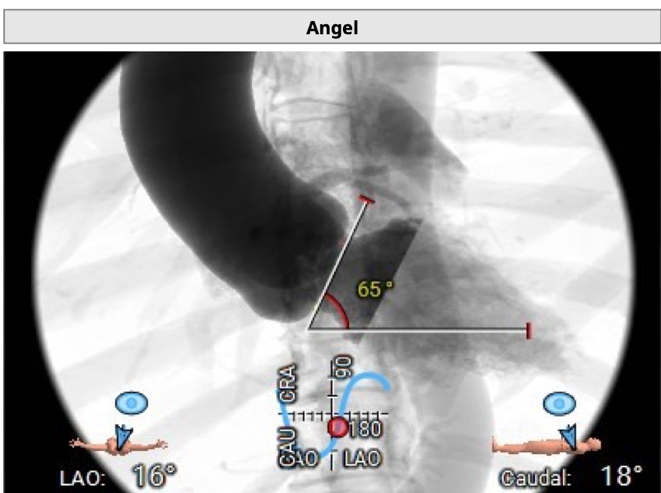

横位心:

手术步骤